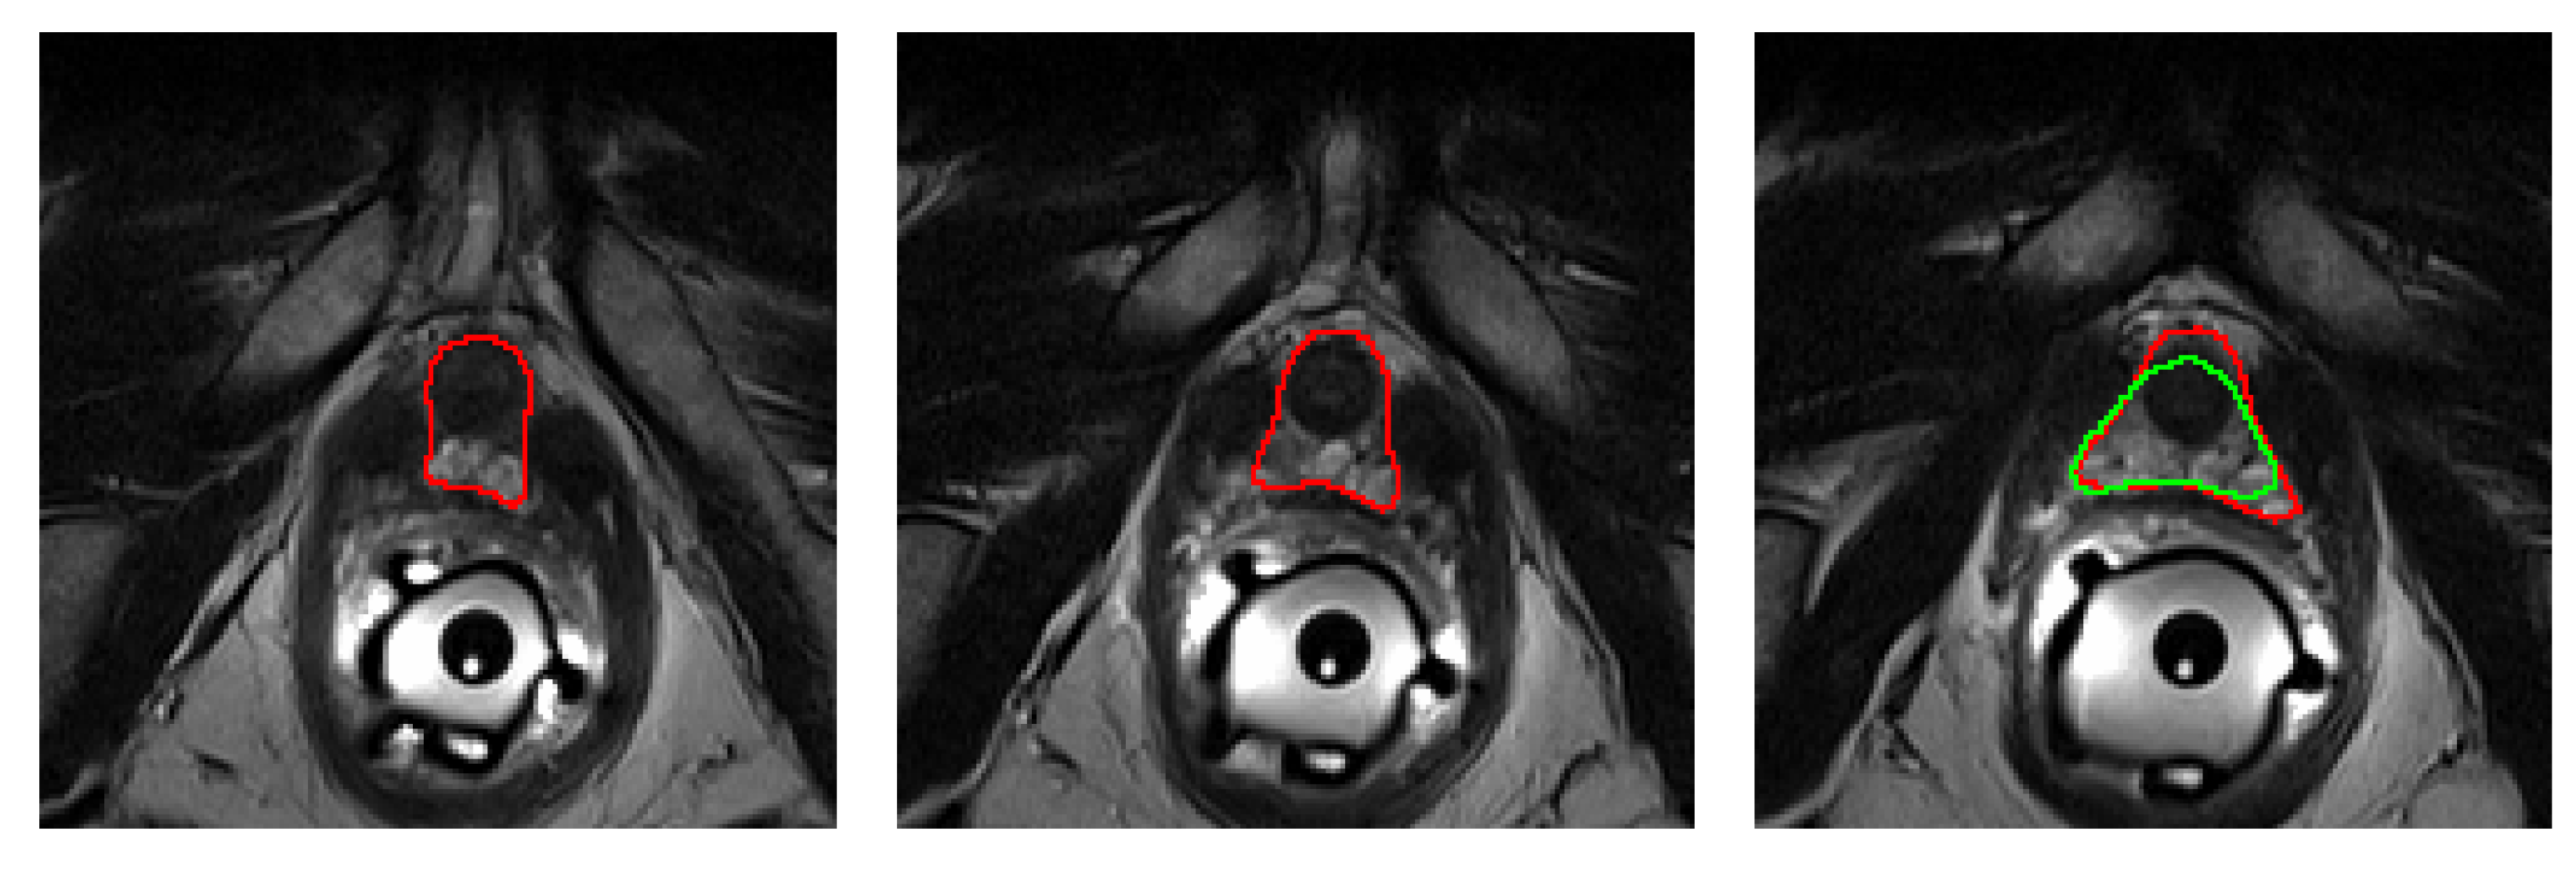

To asses these results qualitatively, in Figure 6a–n, the center 100 mm × 100 mm crop (85 mm × 85 mm in the case of US images) of three slices from the worst and best performing images (in terms of DSC) from each dataset have been represented, along with the GT (in red), the GT2 (in blue, when available) and the predicted segmentations (in green). Figures were generated using Python library plot_lib [38].

Regarding the worst cases, despite being the poorest performers, the differences are relatively small and often the model proposal is arguably superior to the GT. Furthermore, the central slices are almost identical in all instances, and it is only towards base and apex where the differences emerge. One of such discrepancies is the point at which the apex and the base begin, which oftentimes depends on the segmentation criteria, as it can be seen, for instace, in Figure 6a, where the CNN indicates the presence of prostate in the rightmost slice (at the base), while the GT label does not (although GT2 does). Finally, at several ambiguous instances (such as in the middle slice of Figure 6a and the rightmost slice of Figure 6b,j), the predicted mask (in green) behaves as an average between both experts. As discussed, this is a very desirable property for the model to have, and this is what allows it to outperform single experts on their own (as demonstrated in Table 3).

As for the best cases, it can be seen that they are mostly represented by larger prostates, as they are comparatively easier to segment, and also the DSC metric is biased towards them. As a curiosity, the rightmost slice in Figure 6n shows how the model has learned to avoid segmenting the catheter balloon that is used in prostate biopsies, the procedure during which the US images were acquired.

In terms of HD95, the worst MR case, which corresponds to an HD95 of 7.2 mm, is shown in Figure 7. As it can be seen, two slices from the apex are missed by the algorithm, hence amounting to a minimum of 2 × 3 mm of error, plus some extra mm. The worst performing MR case in terms of ABD coincides with the worst performing prostate in terms of DSC, which can be found in Figure 6d.

Figure 7. Worst HD95 (7.2 mm) of all MR test datasets. Two slices from the apex (left and center) are missed by the algorithm, hence amounting to a minimum of 2 × 3 mm of error, plus some extra mm from the segmentation errors commited in the third slice (right).